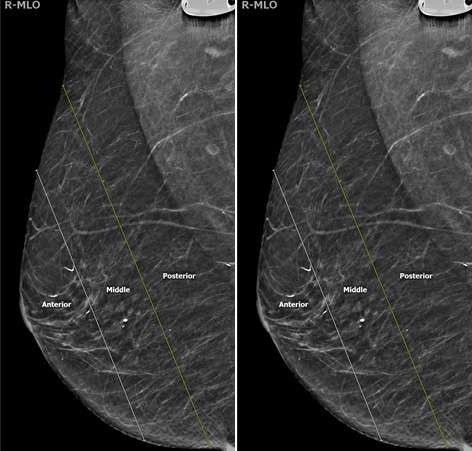

Two additional descriptors can be used to further help localize a lesion: depth within the breast and distance from the nipple. The breast is split into three layers of depth: anterior, middle, and posterior with each depth category representing approximately one-third of the breast tissue (Figure 7).